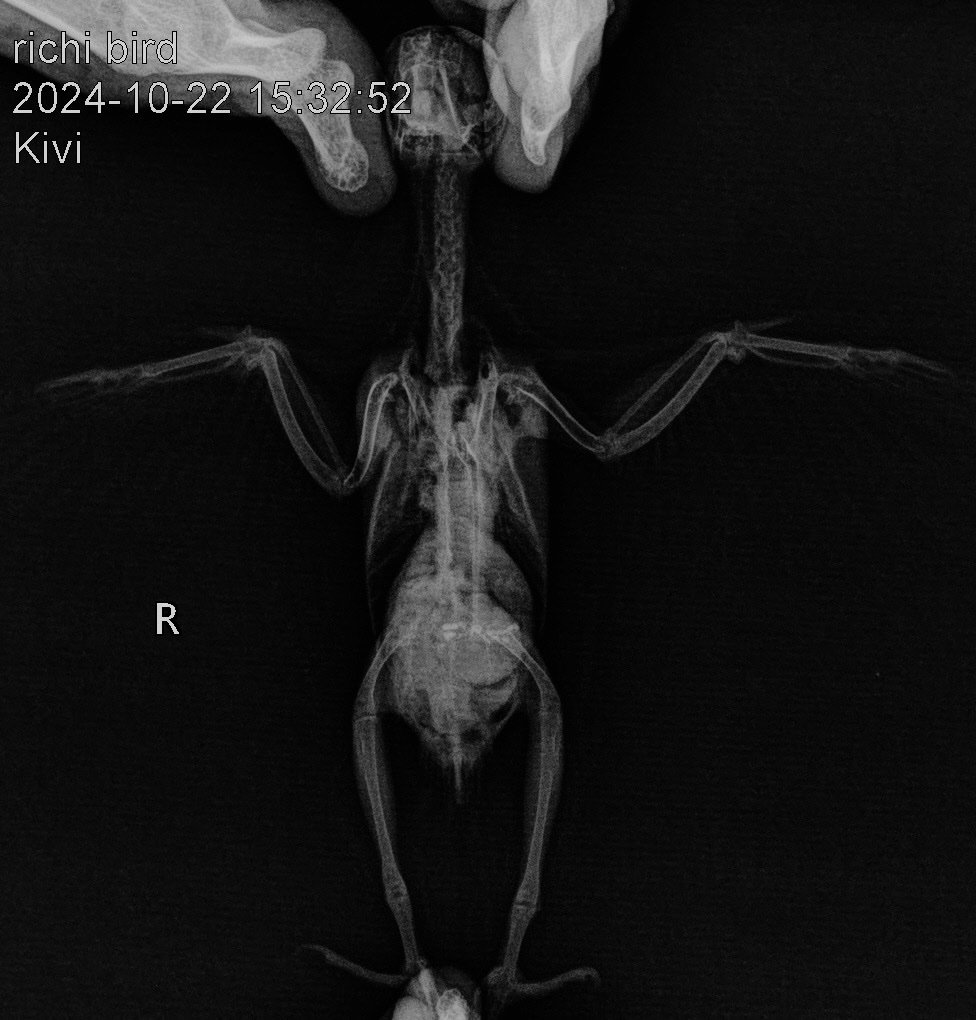

ДианаРикки Опубликовано 23 октября, 2024 #1 Опубликовано 23 октября, 2024 Вчера были на приеме у орнитолога, в Тбилиси. К сожалению, сказали очень печальный прогноз. Вес птицы всего лишь 28 грамм, критический. Сделали рентген, узи. Обнаружили кистообразную опухоль, начало подагры. Прикреплю вам файлы. И диагноз врача. Если вам не сложно, ознакомьтесь, пожалуйста. Сказали только обезбаливать анальгином. Больше никакого лечения. Даже предлагали усыпить, так как птица может испытывать боли, но рука не поднялась. Скажите, пожалуйста, насколько верен диагноз и настолько ли все плачевно или есть какие-то альтернативные варианты лечения? И можно что-то попробовать. Птица клюет шелушит зерна, но не ест. Пытаемся насильно кормить кашей. Отправили домой доживать свои дни. Не назначили никакого лечения, так как вес птицы очень мал. Также сказали не кормить насильно. Но я все де думаю, что опускать руки еще рано и может как-то можно набрать вес, чтобы провести лечение. Ведь подагру можно поддерживать , пока она не распространилась на органы. С каждым днем птице становится хуже. Прикрепляю диагноз врача и снимки рентгена. Спасибо